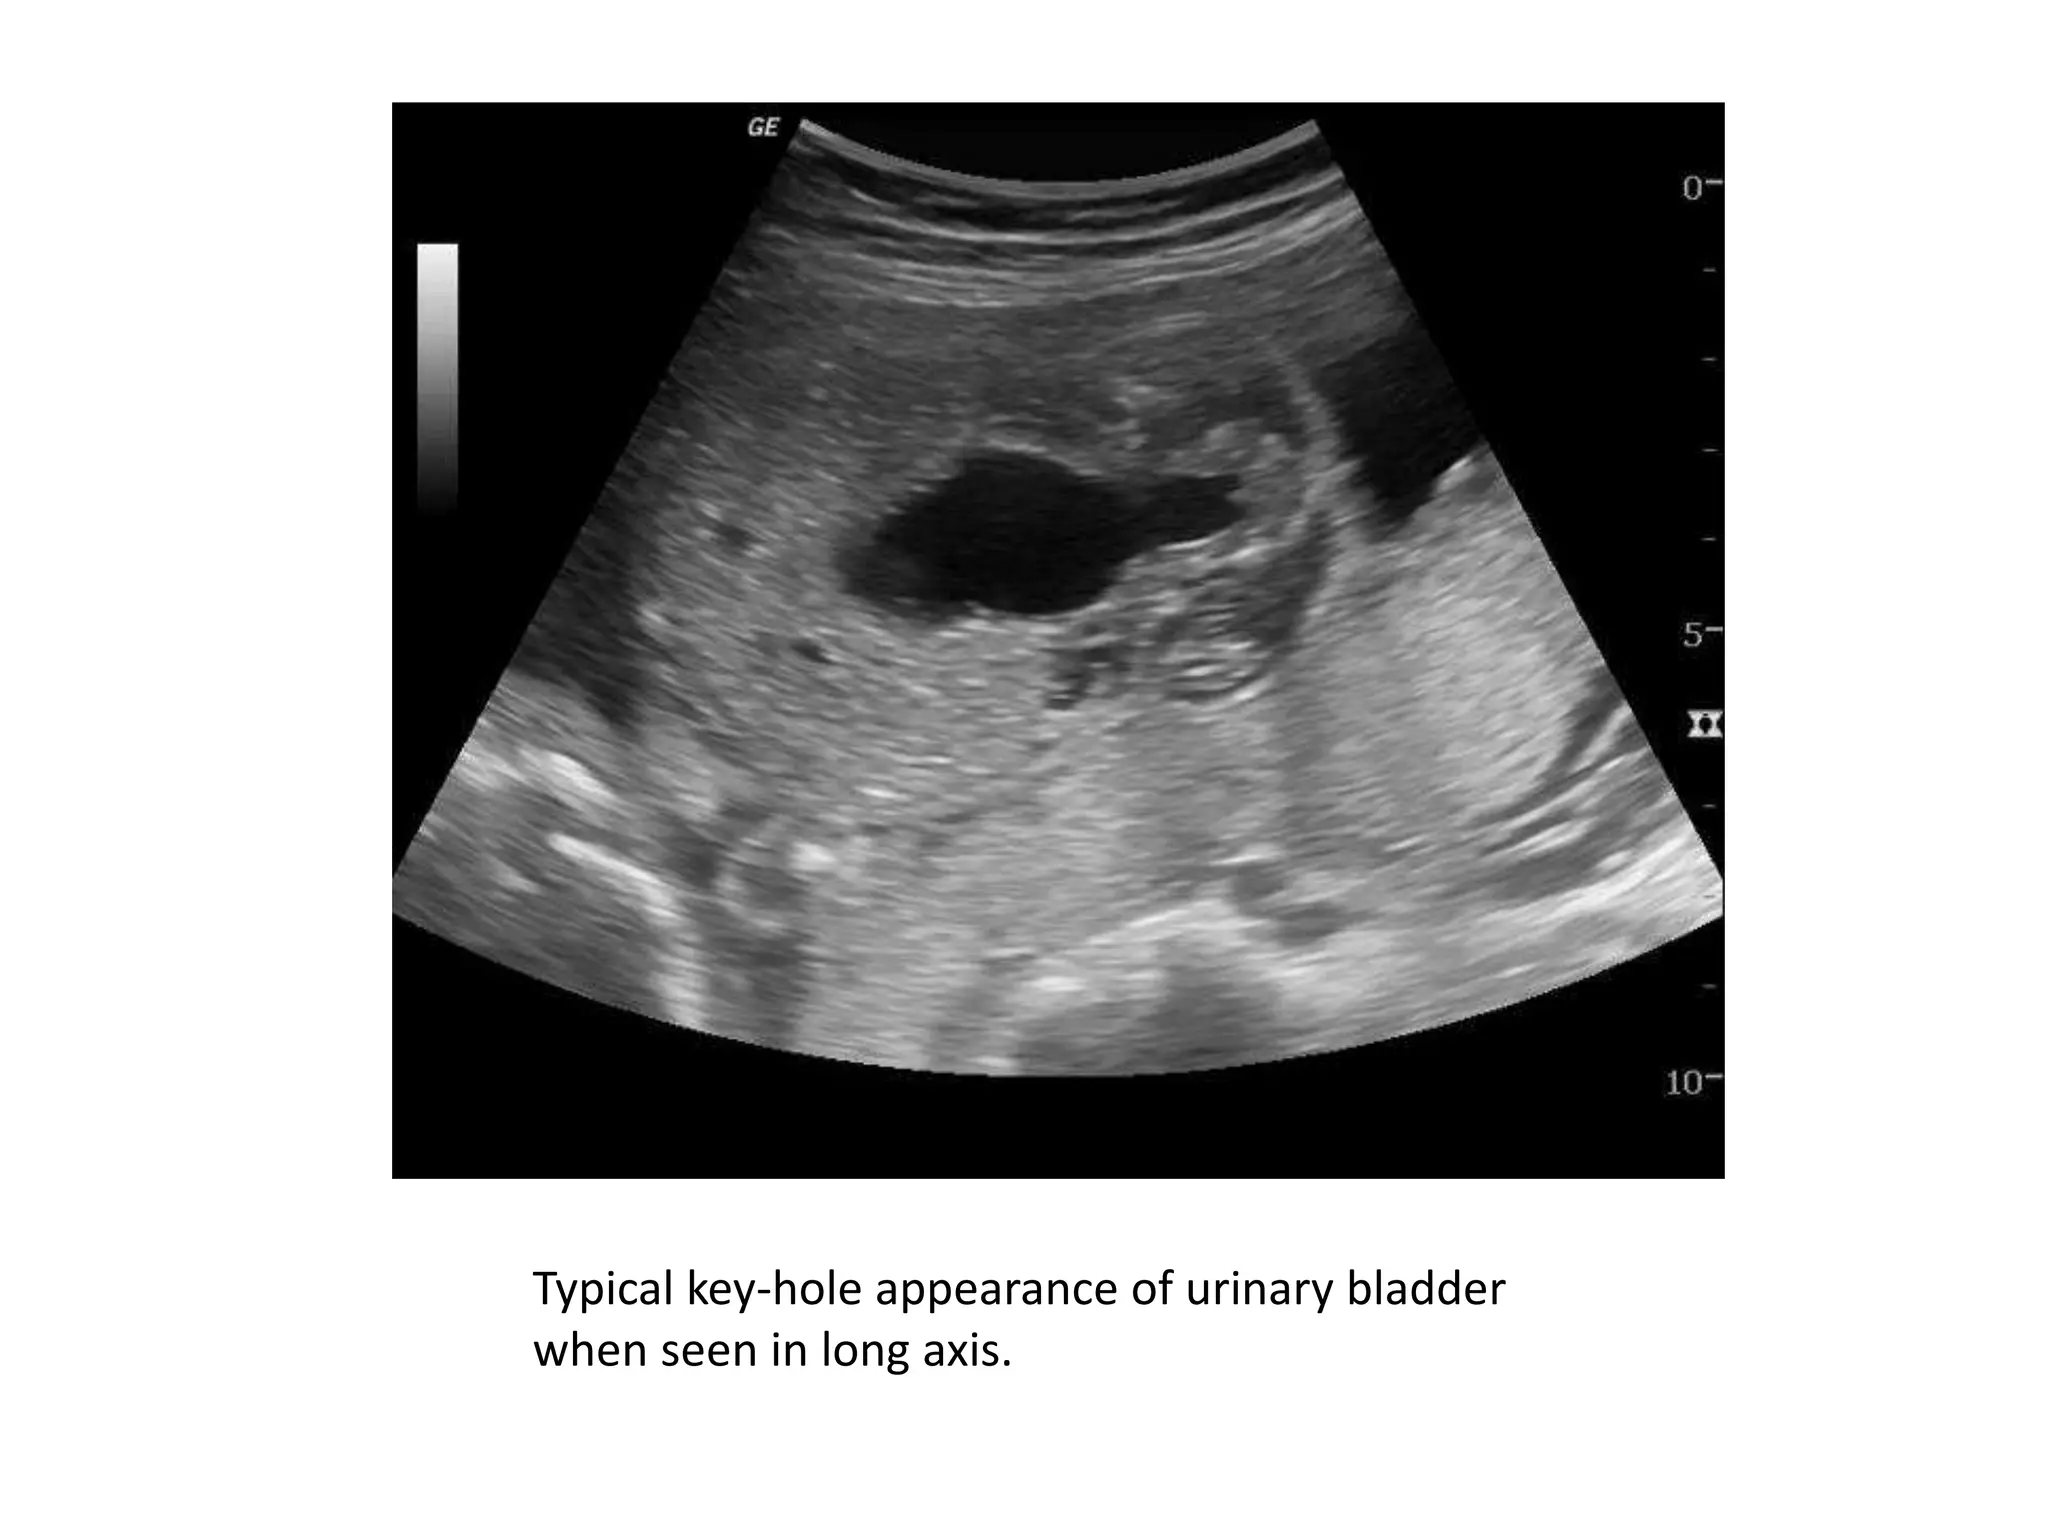

• keyhole sign may be seen on ultrasound due to the

distention of both the bladder and the urethra

immediately proximal to the valve

Typical key-hole appearance of urinary bladder

when seen in long axis.

• Ultrasound • Antenatalultrasound • On antenatal ultrasound the appearance is that of marked distention and hypertrophy of the bladder, hydronephrosis and hydroureter may or may not be present • in severe cases oligohydramnios and renal dysplasia. • keyhole sign may be seen on ultrasound due to the distention of both the bladder and the urethra immediately proximal to the valve • Unfortunately such findings are generally not seen before 26 weeks of gestation, and as such are not frequently identified on routine morphology screening, usually carried out around 18 weeks gestation

Typical key-hole appearanceof urinary bladder when seen in long axis.